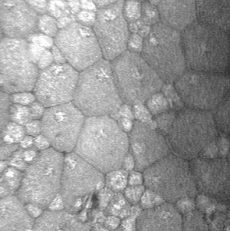

Examen OCT de Edema macular

Examen OCT de: Agujero macular Membrana Epi Macular

Examen OCT de degeneración macular etarea exudativa